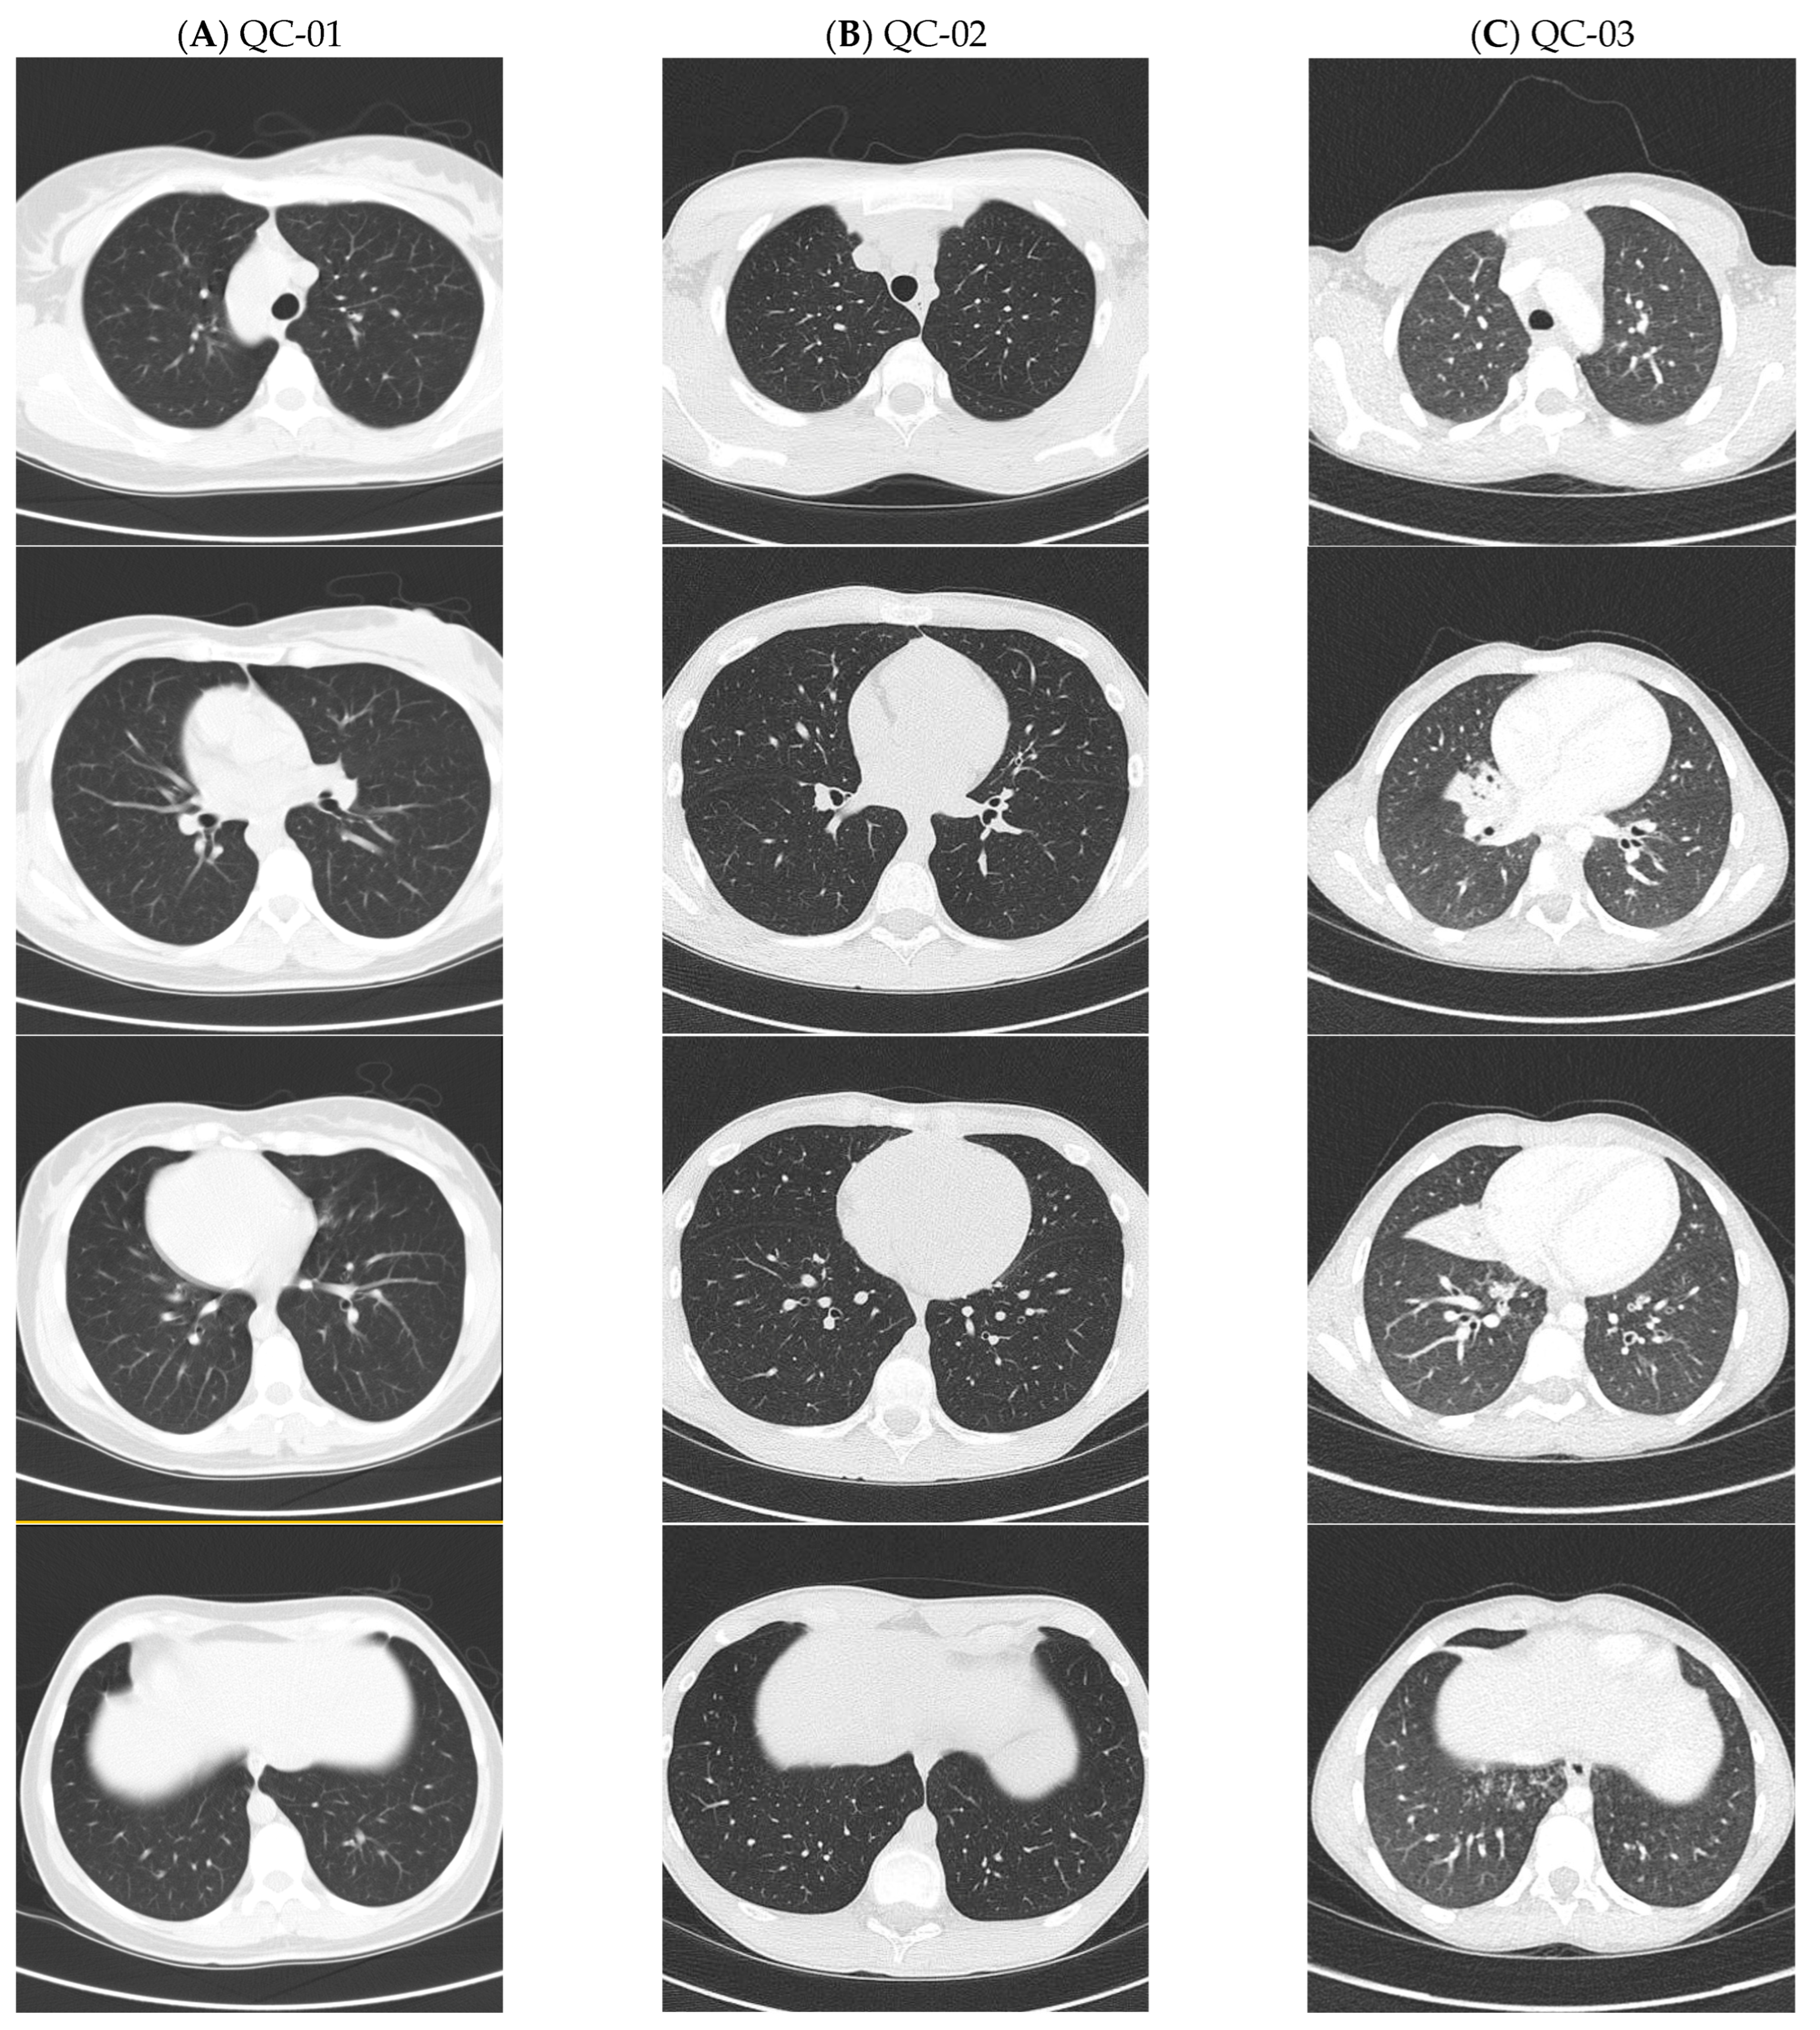

| QC-01 | No | Yes | Yes | Yes | No | No (38) | SIT | 95 | OP flora, MBKub |

| QC-02 | Yes | Yes | Yes | Yes | No | No (14) | SS | 107 | StAur, MCat, StrPne, PsA (eradicated) |

| QC-03 | Yes | No | Yes | Yes | Yes | Yes—RML (8) | SA | 106 | StAur, StrPyo MCat, HFlu |

| NC-01 | No | Yes | Yes | Yes | Yes | Yes—RLL (4) | SIT | 89 | StAur, Hflu, MCat, StrPne, PsA |

| NC-02 | No | Yes | No | Yes | No | CT not done | SIT | 100 | PsA |